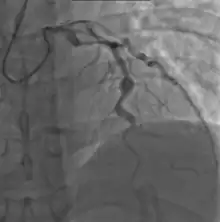

Cardiac

Heart complications are the most important aspect of Kawasaki disease, which is the leading cause of heart disease acquired in childhood in the United States and Japan.[31] In developed nations, it appears to have replaced acute rheumatic fever as the most common cause of acquired heart disease in children.[15] Coronary artery aneurysms occur as a sequela of the vasculitis in 20–25% of untreated children.[52] It is first detected at a mean of 10 days of illness and the peak frequency of coronary artery dilation or aneurysms occurs within four weeks of onset.[48] Aneurysms are classified into small (internal diameter of vessel wall <5 mm), medium (diameter ranging from 5–8 mm), and giant (diameter > 8 mm).[31] Saccular and fusiform aneurysms usually develop between 18 and 25 days after the onset of illness.[15]

Even when treated with high-dose IVIG regimens within the first 10 days of illness, 5% of children with Kawasaki disease develop at the least transient coronary artery dilation and 1% develop giant aneurysms.[53][54][55] Death can occur either due to myocardial infarction secondary to blood clot formation in a coronary artery aneurysm or to rupture of a large coronary artery aneurysm. Death is most common two to 12 weeks after the onset of illness.[15]

- Angiography was historically used to detect coronary artery aneurysms, and remains the gold standard for their detection, but is rarely used today unless coronary artery aneurysms have already been detected by echocardiography.

Laboratory evidence of increased inflammation combined with demographic features (male sex, age less than six months or greater than eight years) and incomplete response to IVIG therapy create a profile of a high-risk patient with Kawasaki disease.[58][152] The likelihood that an aneurysm will resolve appears to be determined in large measure by its initial size, in which the smaller aneurysms have a greater likelihood of regression.[153][154] Other factors are positively associated with the regression of aneurysms, including being younger than a year old at the onset of Kawasaki disease, fusiform rather than saccular aneurysm morphology, and an aneurysm location in a distal coronary segment.[60] The highest rate of progression to stenosis occurs among those who develop large aneurysms.[4] The worst prognosis occurs in children with giant aneurysms.[155] This severe outcome may require further treatment such as percutaneous transluminal angioplasty,[156] coronary artery stenting,[157] bypass grafting,[158] and even cardiac transplantation.[159]